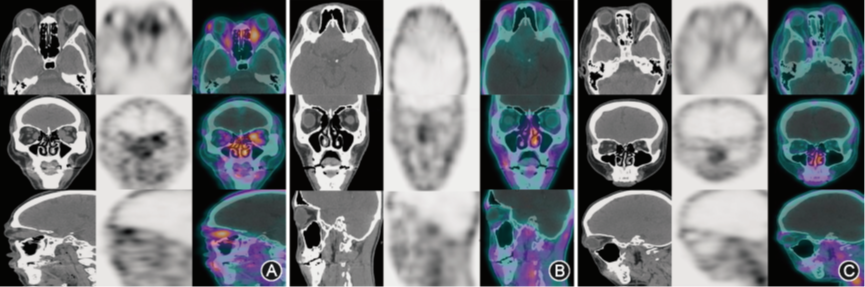

99Tcm‑二乙烯三胺五乙酸(diethylenetriaminepentaacetic acid,DTPA)是一种敏感的炎性活动标志物,目前已于核医学科常规开展使用。活动期TAO患者可见放射性核素在眼外肌、泪腺、球后脂肪组织等眼眶组织中异常浓聚、增强,放射性核素摄取明显增高(图5中A)。非活动期TAO患者放射性核素摄取轻度增高(图5中B)。健康志愿者无明显或仅有轻度的放射性核素摄取,表现为“冷区”(图5中C)

图5 不同活动期TAO及健康志愿者的SPECT/CT显像

A示甲状腺相关眼病(TAO)活动期组患者,放射性核素在眼外肌、泪腺、球后脂肪组织等眼眶组织中异常浓聚、增强;B示TAO非活动期组患者,放射性核素摄取轻度增高;C示对照组健康志愿者,无明显或仅有轻度的放射性核素摄取。SPECT/CT是一台将CT解剖和SPECT功能显像仪同时安装在一个整体里的多模态影像设备,完成一次SPECT/CT检查,能同时获得眼眶的功能代谢信息图像和解剖诊断信息图像,其具有灵敏度和准确度高,特异性强及定位准确等优点。CAS评分结合相关影像学检查,可以成为评价TAO临床活动性的有益补充。近年来,眼眶SPECT/CT检查在多个中心逐渐开始应用于TAO的临床活动性的分期评价。TAO活动期患者的放射性核素摄取明显增高,核素在眼外肌、泪腺、球后脂肪组织等眼眶组织中异常浓聚、增强;TAO非活动期患者的放射性核素摄取轻度增高;活动期与非活动期二者之间的差别明显,通过医师阅片即可区分。使用的新款SPECT/CT分析软件,可对数据进行迭代重建、散射修正、衰减校正等操作,计算得到最大放射性核素浓度即SUVmax值,实现了定量分析放射性核素摄取值,具有操作方法简单、可重复性好的优势。综上所述,一方面,对于存在眼表暴露情况的TAO患者,临床医生往往容易高估CAS评分,导致TAO分期判断的准确性明显降低;另外一方面,由于眼表的炎性反应可以掩盖眶内真实的炎性反应状态,在评估TAO病程时容易导致临床医师误判;最后,据报道眼眶内炎性反应无法通过CAS得分准确体现。在这些场景下,99Tcm‑DTPA 眼眶SPECT/CT显像可有效弥补CAS评分的不足,能更客观、相对准确地评估眼眶内的炎性反应真实状态,从而更准确地提示临床医生,为临床治疗决策提供帮助。